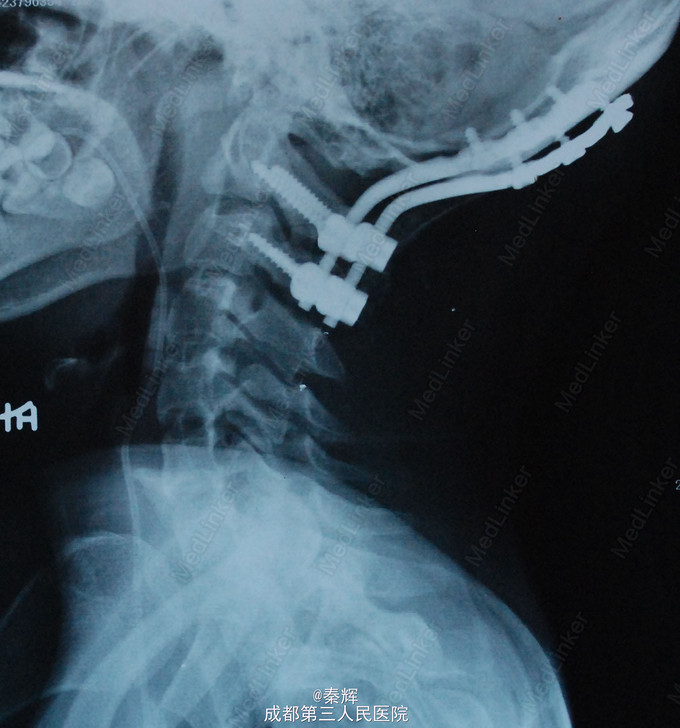

诊断“颅底凹陷、脊髓空洞”,行牵引复位、枕骨大孔扩大、枕颈融合、内固定术。

术后半年复查症状缓解。 颅底凹陷症是以枕骨大孔为中心的颅底骨组织、寰椎及枢椎骨质发育畸形,寰椎向颅腔内陷入,枢椎齿状突高出正常水平进入枕骨大孔,使枕骨大孔狭窄,后颅窝变小,从而压迫延髓、小脑及牵拉神经根产生一系列症状,或有椎动脉供血不足表现,可同时伴有脊髓空洞。